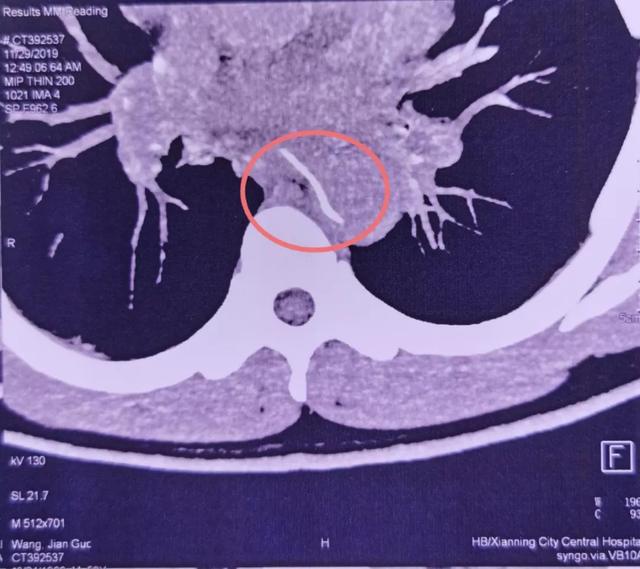

家人连忙拍背 , 让他吞米饭 , 把鱼刺咽下去 。 然而并没有效果 。 曹先生紧忙赶到当地医院 。 CT检查发现 , 一根鱼刺状异物横卧在食管 , 已经刺穿食管壁 , 尖头紧贴心脏主动脉!

情况紧急 , 曹先生和家人立即奔赴武汉大学人民医院 。 此时 , 距他误吞鱼刺 , 已有6个多小时 。

了解情况后 , 该院胸外科耿庆教授团队联合心血管外科、消化内科、放射科、麻醉科等 , 组建MDT团队 , 紧急分析讨论病情后一致认为:任何轻微的外力刺激 , 都可能使鱼刺刺穿血管 , 致大出血 , 患者随时可能猝死;食管已被刺破 , 引发感染 , 死亡率也很高 。

救治团队当机立断 , 将其送入手术室 , 行全麻下急诊开胸探查 。 胸外科耿庆教授和汪巍副教授联手 , 从左侧开胸探查胸腔 , 小心翼翼松解胸腔粘连 , 清理干净分泌物后 , 发现鱼刺已刺穿食管 。 鱼刺尖端正处于主动脉弓下方 , 距离主动脉弓仅有1毫米 , 差点就要伤及主动脉 。